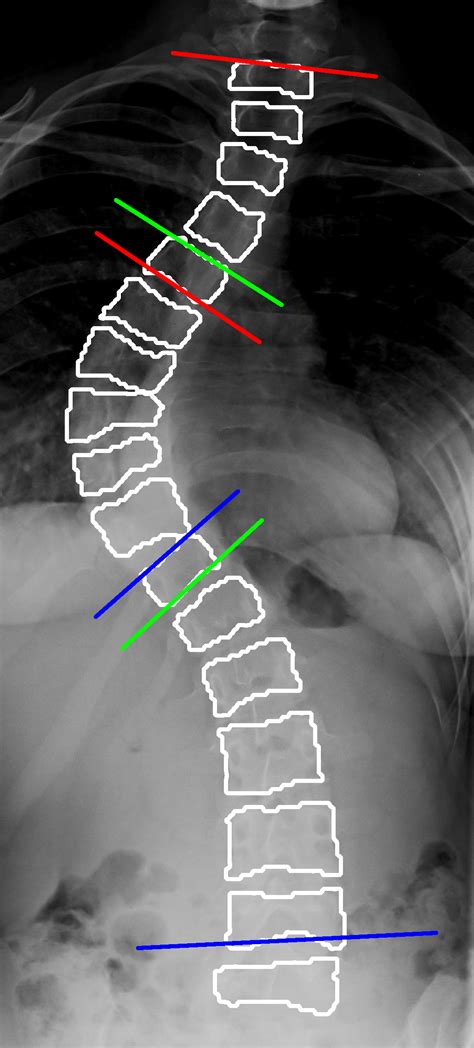

• Obtain an X-ray of the spine, typically a standing posterior-anterior (PA) view.

• Identify the most tilted vertebrae at the top and bottom of the curve.

• Draw a line along the endplate of each of these vertebrae.

• Draw perpendicular lines to these endplate lines.

• Measure the angle formed by the intersection of these perpendicular lines.

This angle is the Cobb Angle Scoliosis, and it provides a quantitative measure of the spinal curvature.